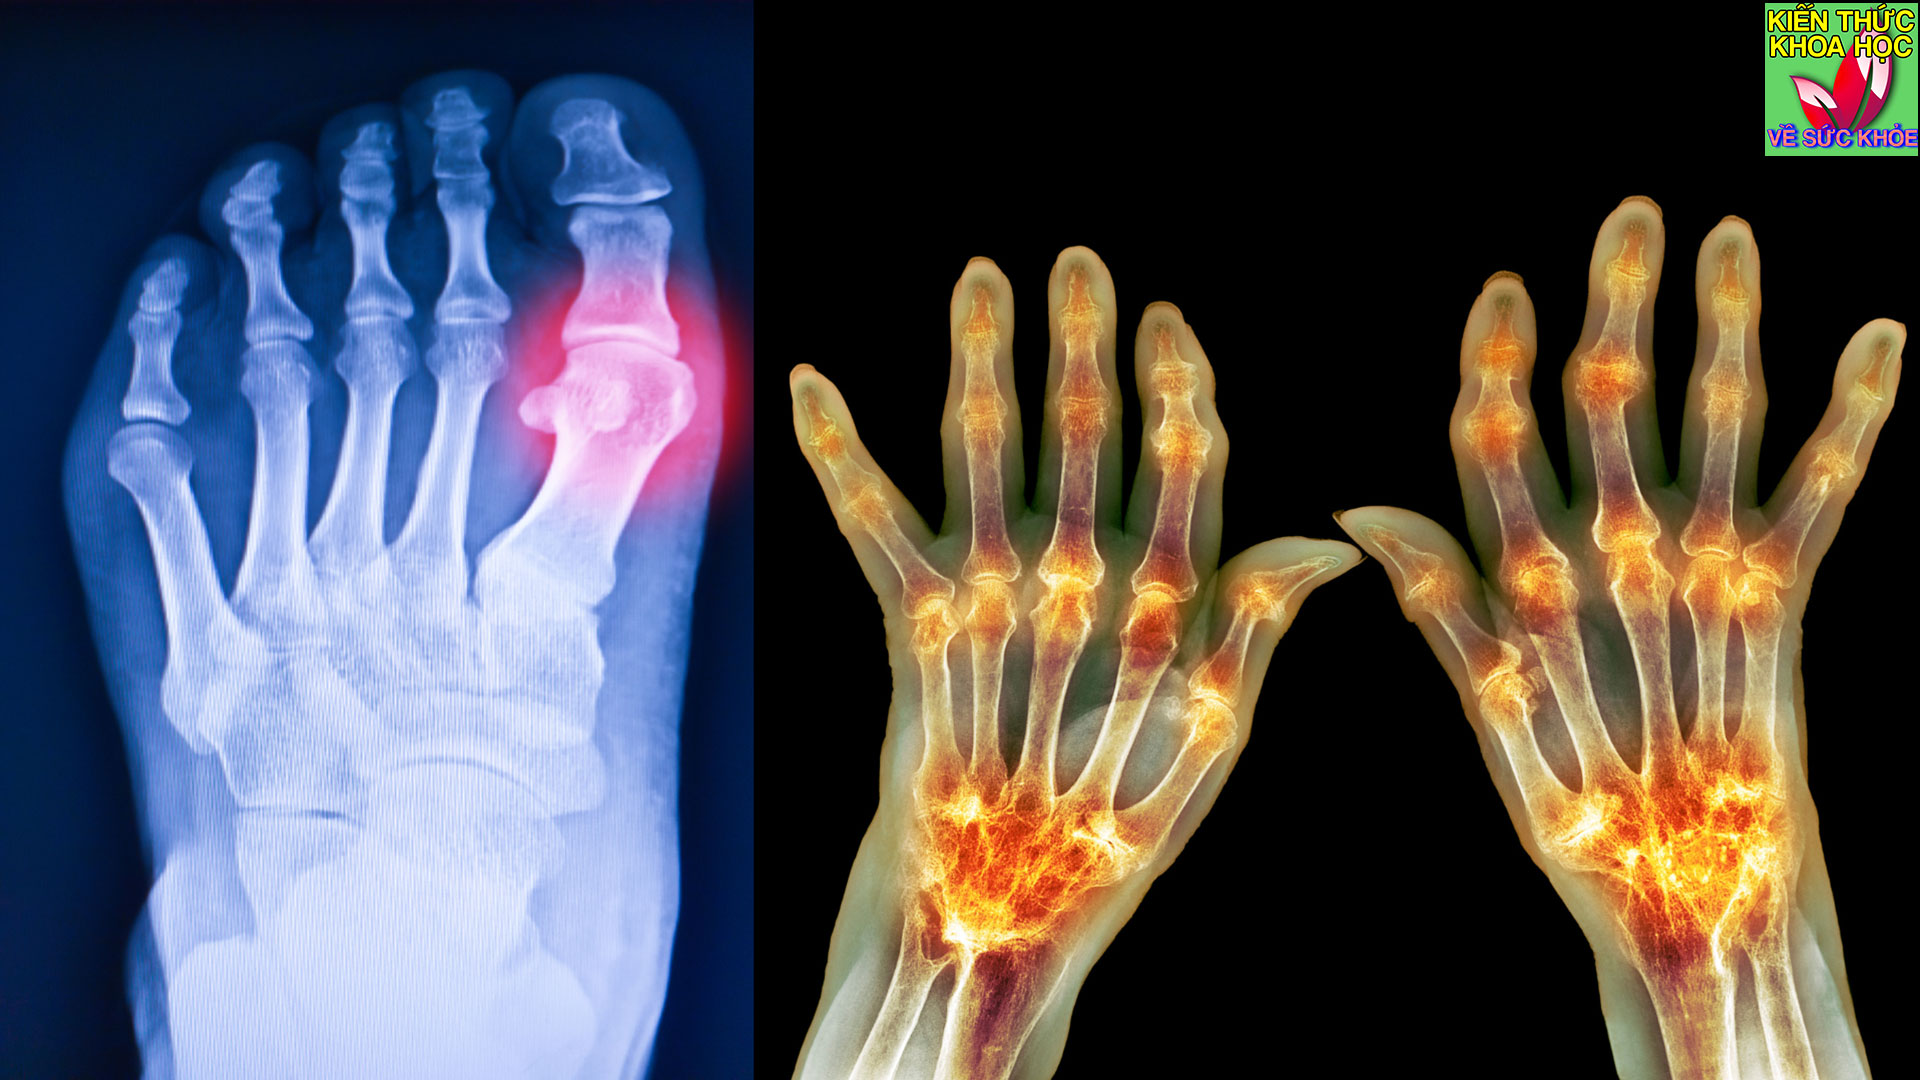

Vitamin C là một chất chống oxy hóa hoạt động giống như thuốc giảm đau đối với chứng đau xương, khớp hoặc cơ bắp, bảo vệ chống lại các gốc tự do là những phân tử không ổn định có thể làm hư hỏng tế bào.

Vitamin C có thể góp phần ngăn ngừa các triệu chứng viêm khớp, duy trì khớp khỏe mạnh và phục hồi sau chấn thương. Vitamin C đặc biệt giúp ích cho bệnh viêm khớp nhờ khả năng thúc đẩy tổng hợp collagen và hồi phục gân.

Khi bị viêm khớp hoặc bệnh gout, điều quan trọng là phải uống đủ nước. Nước chanh là sự thay thế lành mạnh cho nước ngọt hoặc đồ uống có đường và có những lợi ích cụ thể cho người bệnh viêm khớp.